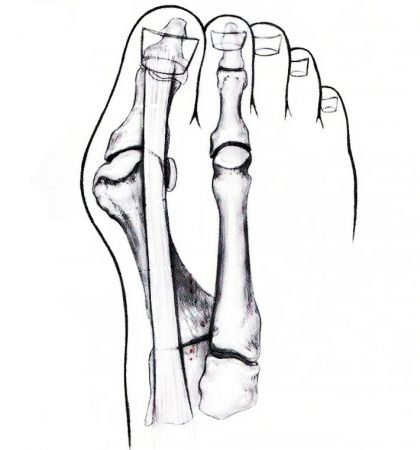

Hallux valgus is een zeer frequent voorkomende afwijking. Hallux is de Latijnse term voor grote teen en met valgus bedoelt men dat de grote teen steeds meer afwijkt van de rechte as in de richting van de kleine teen. Hierdoor ontstaat steeds meer een beenderige knobbel aan de binnenzijde van de voet (bunion) De klachten zijn van persoon tot persoon zeer wisselend, maar verlopen toch meestal in grote fases. In de beginfase kan de knobbelvorming, zelfs bij een kleine afwijking, zeer veel ongemak in de schoenen teweegbrengen. Naarmate de afwijking toeneemt, wijken de pezen steeds meer van hun traject af en gaan ze volgens het ‘boogprincipe’ de teen steeds meer doen afwijken. Hierdoor wordt de kracht bij het afduwen steeds meer verschoven naar de buitenzijde van de voorvoet met pijn tot gevolg. In een nog verder stadium gaat de grote teen zich onder de tweede teen positioneren en ontwikkelt zich thv. deze tweede teen een hamerteenmisvorming. De tweede teen wordt geleidelijk uit zijn gewricht gelicht. In de beginfase gaat het gepaard met felle pijn. Eens de teen volledig uit het gewricht is geduwd, is de afwijking meestal zeer uitgesproken, maar in veel gevallen ook weer minder pijnlijk. De oorzaak is niet helemaal duidelijk, maar in vele gevallen is er een familiale aanleg en is er een voorkeur voor het vrouwelijke geslacht. Ook het dragen van zeer nauw aansluitende schoenen met hak kan meespelen in het ontwikkelen van de afwijking. In gevallen van familiale aanleg, kan de aandoening soms al op heel jonge leeftijd duidelijke vormen aannemen (juveniele hallux valgus)

Hallux valgus is een zeer frequent voorkomende afwijking. Hallux is de Latijnse term voor grote teen en met valgus bedoelt men dat de grote teen steeds meer afwijkt van de rechte as in de richting van de kleine teen. Hierdoor ontstaat steeds meer een beenderige knobbel aan de binnenzijde van de voet (bunion) De klachten zijn van persoon tot persoon zeer wisselend, maar verlopen toch meestal in grote fases. In de beginfase kan de knobbelvorming, zelfs bij een kleine afwijking, zeer veel ongemak in de schoenen teweegbrengen. Naarmate de afwijking toeneemt, wijken de pezen steeds meer van hun traject af en gaan ze volgens het ‘boogprincipe’ de teen steeds meer doen afwijken. Hierdoor wordt de kracht bij het afduwen steeds meer verschoven naar de buitenzijde van de voorvoet met pijn tot gevolg. In een nog verder stadium gaat de grote teen zich onder de tweede teen positioneren en ontwikkelt zich thv. deze tweede teen een hamerteenmisvorming. De tweede teen wordt geleidelijk uit zijn gewricht gelicht. In de beginfase gaat het gepaard met felle pijn. Eens de teen volledig uit het gewricht is geduwd, is de afwijking meestal zeer uitgesproken, maar in veel gevallen ook weer minder pijnlijk. De oorzaak is niet helemaal duidelijk, maar in vele gevallen is er een familiale aanleg en is er een voorkeur voor het vrouwelijke geslacht. Ook het dragen van zeer nauw aansluitende schoenen met hak kan meespelen in het ontwikkelen van de afwijking. In gevallen van familiale aanleg, kan de aandoening soms al op heel jonge leeftijd duidelijke vormen aannemen (juveniele hallux valgus)

Grosso modo kan men stellen dat bij lichte of mildere afwijkingen, er beenderige correcties aan de voorvoet worden uitgevoerd, zoals de Chevron- of de scarfosteotomie, al of niet in combinatie met een beperkte correctie van de teen zelf. (Akin) Dergelijke operaties zijn meestal heel stabiel en na enkele dagen kan met een speciale postoperatieve schoen reeds steun worden toegestaan gedurende een vijftal weken. Indien de afwijking meer uitgesproken is, moet soms een correctie worden uitgevoerd in de middenvoet. Het gevolg is dat hiervoor meestal een zestal weken gipsimmobilisatie nodig is, over het algemeen met een steunverbod gedurende de eerste vier weken.